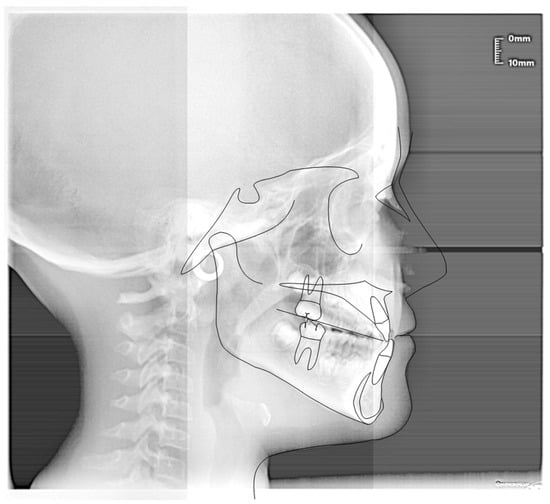

3.1. Clinical Case #1